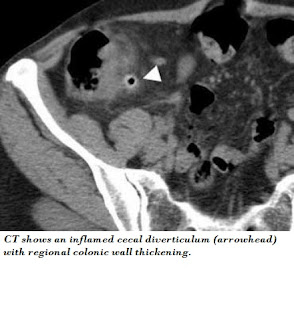

Acute Abdomen.